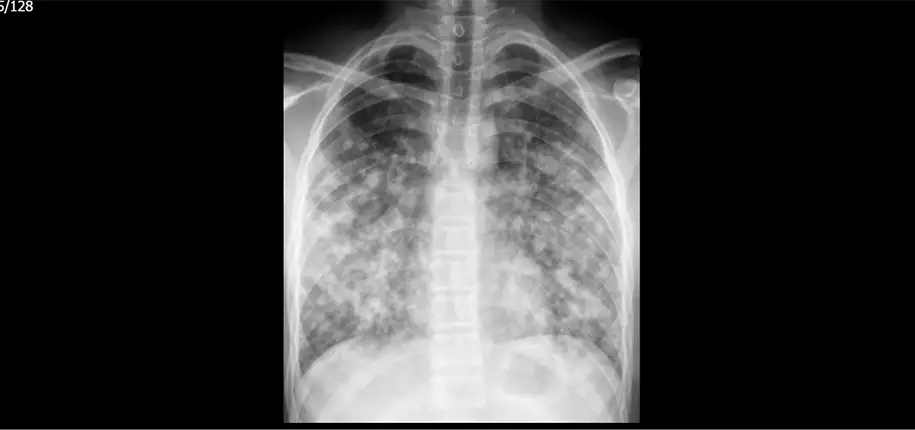

“WOPR, you know better than that. A chest X-ray tells you what’s going on when you get it, not what was going on before or what will happen afterwards. What was going on when she got the chest X-ray?”

“Sounds to me like the system worked just the way it should. Ella’s pediatrician diagnosed and treated her for pneumonia. Her mom listened to the pediatrician who said to bring her back if she wasn’t better in a week. When her pediatrician saw that she was still coughing, she got a chest X-ray to make sure that there wasn’t anything to suggest a worsening pneumonia or some other cause for her cough. How’s she doing?”

“WOPR, two more things. First, I don’t want anyone to think that it’s a mistake to get a chest X-ray right away for pneumonia. There are clues to what’s going on that can be useful. Sometimes the chest X-ray looks much worse than we thought it would, and sometimes much better. In both those cases it could change how we take care of the child. There are lots of things that can make it hard to breath besides pneumonia, and a chest X-ray can be a good way to make sure that none of those are going on. It’s a judgement call.”